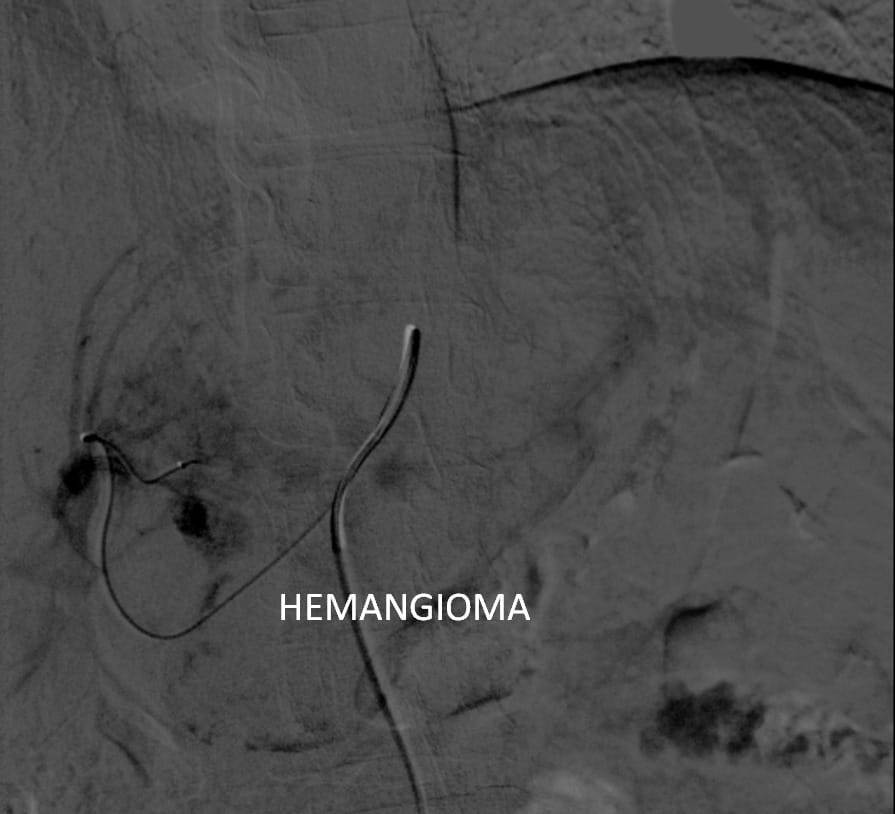

وتعتبر هذه العملية الأول من نوعها يتم علاجها من خلال جهاز الأشعة المقطعية ١٢٨ متعدد المقاطع حيث تم علاج الورم من خلال قسطرة بالشريان الكبدي للفص الأيسر من الكبد ونجاح عملية الحقن التي تظهر اختفاء الأوعية الدموية المغذية للورم.